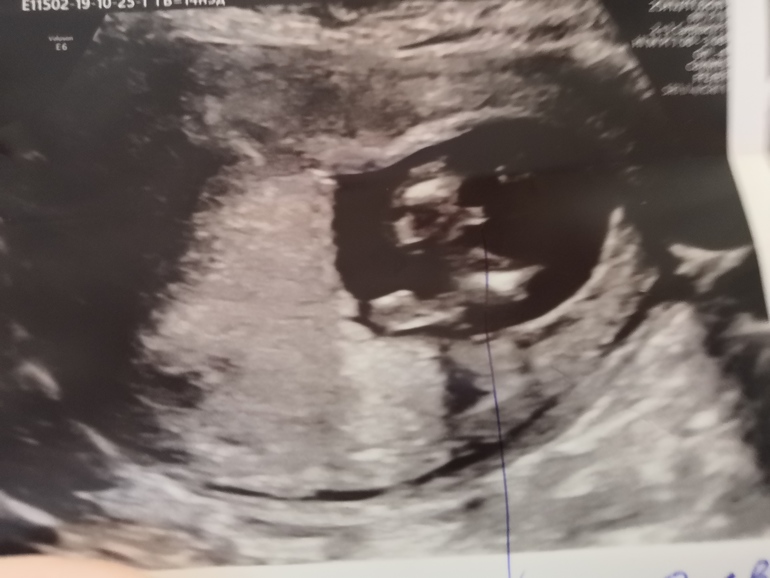

Фото снизу

Скажите, а на нижнем фото ручкой отмечено, это что?это с последнего узи когда предположили мальчика?

Да, всё верно. Врач долго меня мурыжила и на бок и на спину, хотела пол показать, я же платно скрининг повторно делала и вот предположила нам мальчика. Только снизу, якобы, рассмотрела.

Снизу прям мальчик, а сверху девочка... Желаю вам чтобы это оказалась дочечка)